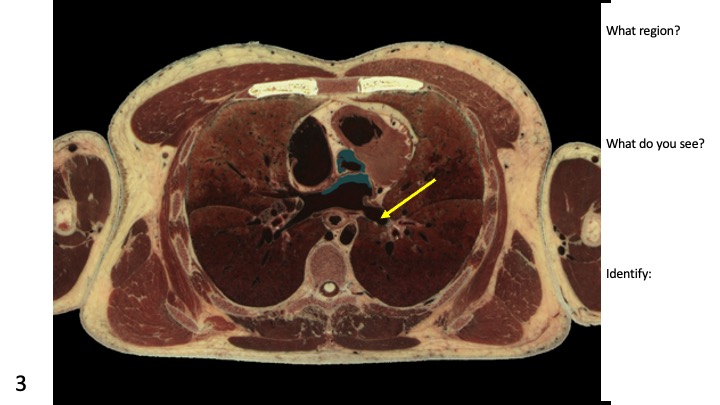

Our #VHDissector’s true color labeled cross-sectional images are an integral part in @BUAnatNeuro's anatomy lab and lectures for MD and PA students. Exposure to anatomical structures and spatial relationships in the cross-sections helps better prepare learners for their careers!